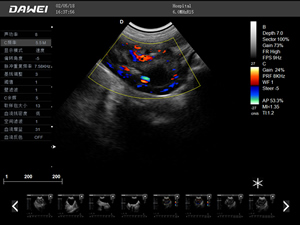

·支持彩色多普勒、頻譜多普勒、能量多普勒、連續多普勒等成像技術